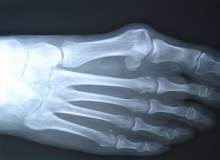

Cam kemik hastalığı, kemiklerde kolay ve sık kırılmanın yanısıra mavi sklera, diş bozuklukları ve işitme bozukluklarının da birlikte görülebildiği bir hastalıktır.